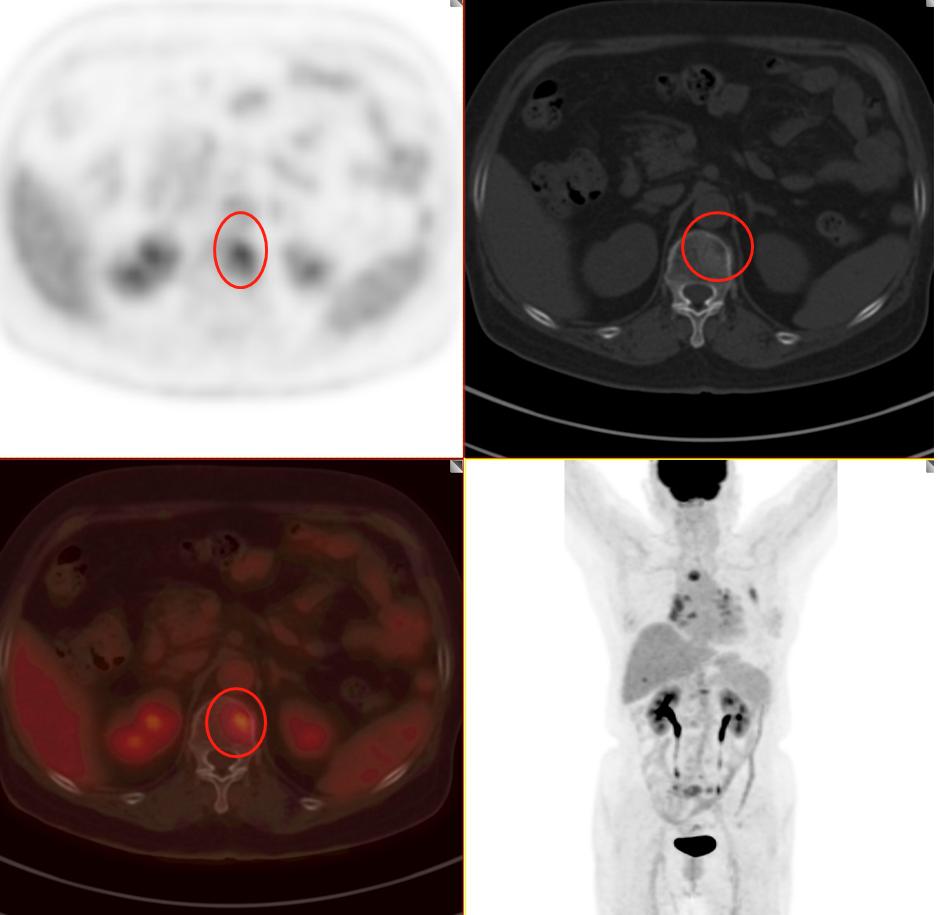

患者2:图5

图4-5分别提示:胸骨、腰椎、骶骨及右侧髂骨骨转移。